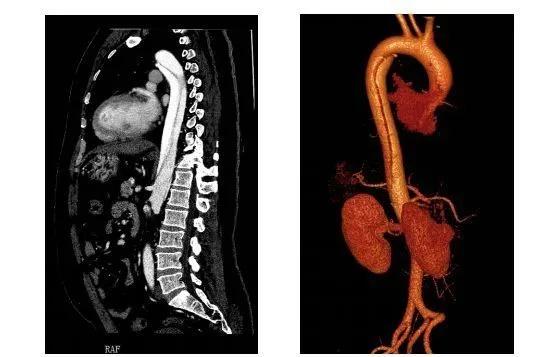

主动脉是人体最粗大的主干血管,直接由心脏发出,承受直接来自心脏泵血强大压力。正常人体动脉血管壁由三层结构组成,由内而外分别是内膜、中层和外膜,三层结构紧密贴合,共同承受血流的压力。主动脉夹层是指主动脉内膜局部出现破口,主动脉腔内的血液从破口进入主动脉壁间隙内,使主动脉壁中层剥离,强有力的血液继续冲击且沿主动脉纵轴扩展,内膜逐步剥离,在动脉内形成真、假两腔,形成夹层,并导致难以忍受的撕裂样疼痛。

根据主动脉内膜裂口的位置和夹层累及的范围,目前医学上有两种主要的分类方法。

确诊主动脉夹层的主要辅助检查手段是:CT血管造影(CTA),磁共振检查(MRA)或是直接的数字剪影血管造影(DSA)。其中CTA检查速度快,是最主要的检查,对于孕妇可以做MRA无放射线辐射,对胎儿也没有影响。